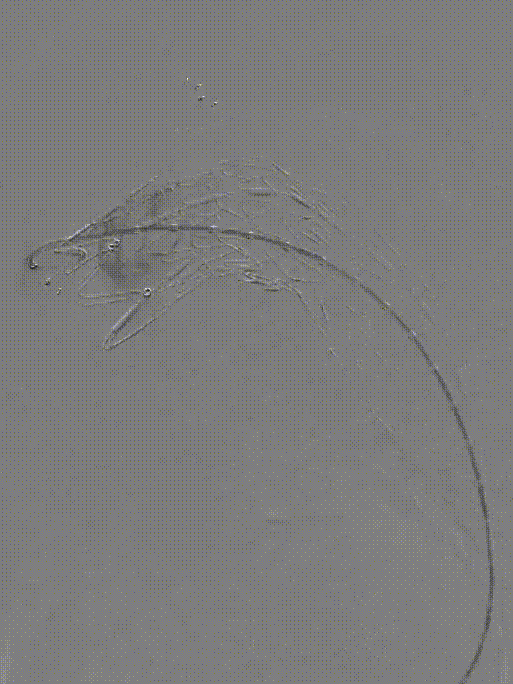

LSA弹簧圈栓塞

造影内漏消失